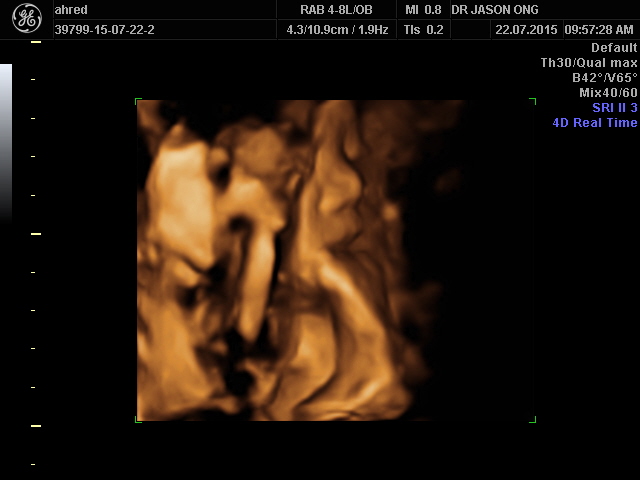

第七次产检 @ 22/7/2015

小宝没有眼看吗?!!XD

小宝在吃脚叻

有没有这么饿呀?!!